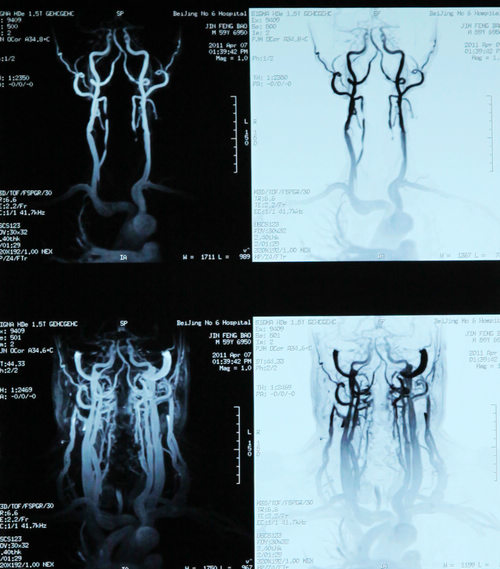

双侧颈动脉狭窄,反复头晕2年

患者金某某,男,58岁,主因反复头晕2年,加重伴左侧肢体麻木1年入院。患者2年前无明显诱因突然出现头晕,伴左侧肢体力弱,无明显头痛、恶心。呕吐,无视物旋转、耳鸣、听力下降、黑曚、晕厥、肢体抽搐,于当地医院行头颅CT检查示双侧多发腔隙性脑梗塞。给予改善脑循环、降压等药物治疗(具体不详)后症状好转。1年前无诱因再发头晕不适,伴左侧肢体麻木,偶有黑曚出现,无肢体力弱、耳鸣、视物旋转。于当地医院保守治疗后好转。住院期间行造影提示左侧颈内动脉狭窄。为进一步治疗入住北京市第六医院。

颈动脉超声:双侧颈动脉粥样硬化斑块形成;双侧颈内静脉未见明显异常。

双侧颈内动脉狭窄

患者为高龄男性,“反复头晕2年,加重伴左侧肢体麻木1年”,有高血压、糖尿病、高脂血症,双侧颈内动脉狭窄,属脑卒中高发人群,实施CEA手术可有效预防卒中发作。2011年4月12日,协作组张勤奕教授及安贞医院欧阳川教授顺利为其实施了左侧颈动脉内膜剥脱术。